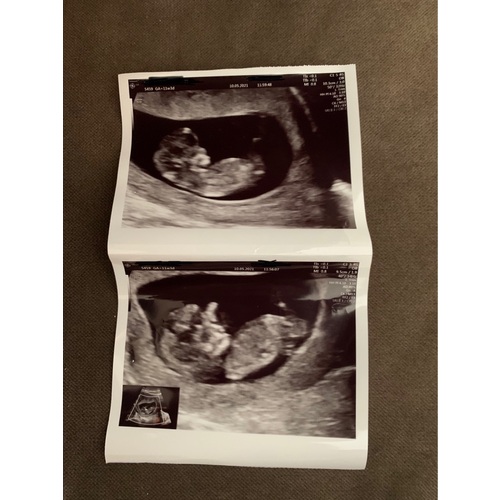

Hierbij nog een foto

Is het hierop duidelijker ?

.

Nee het is te vroeg om het te kunnen zien!

Je ziet nub vanaf 12/13 weken wat beter en 14 zie je het al redelijk goed